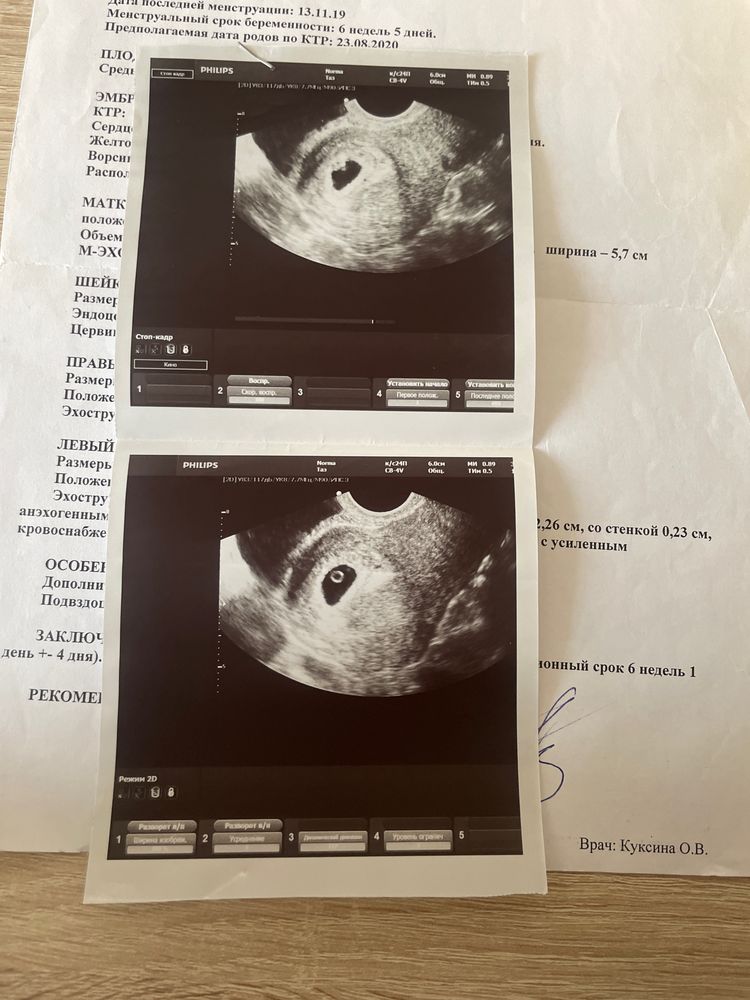

Первое фото 6 н + 4 д, второе 10 н - совсем не круглое, но я думаю все зависит от ракурса.